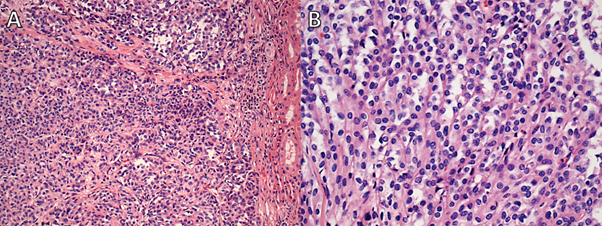

The following lesions were also found in the kidney: a nodular lesion present in the upper pole (35 mm at largest dimension) classified as clear-cell (cc) RCC (WHO/ISUP grade 3); and two additional nodules (8 and 9 mm at largest dimension) were identified in the lower pole, both classified as papillary adenomas. Both of these lesions were initially classified as type 1 papillary RCC (grade 2); however, these lesions were reclassified by a uropathologist as papillary adenomas, based on the World Health Organization 2016 classification of adult renal tumours (lesions are <15 mm at largest dimension) (6). All tumours were confined to the kidney (Figure 3).

Figure 3

Figure 3. Case 1: A and B. Clear-cell renal cell carcinoma, grade 3; high- and low-power fields of the two papillary adenomas are shown in C and D and E and F.